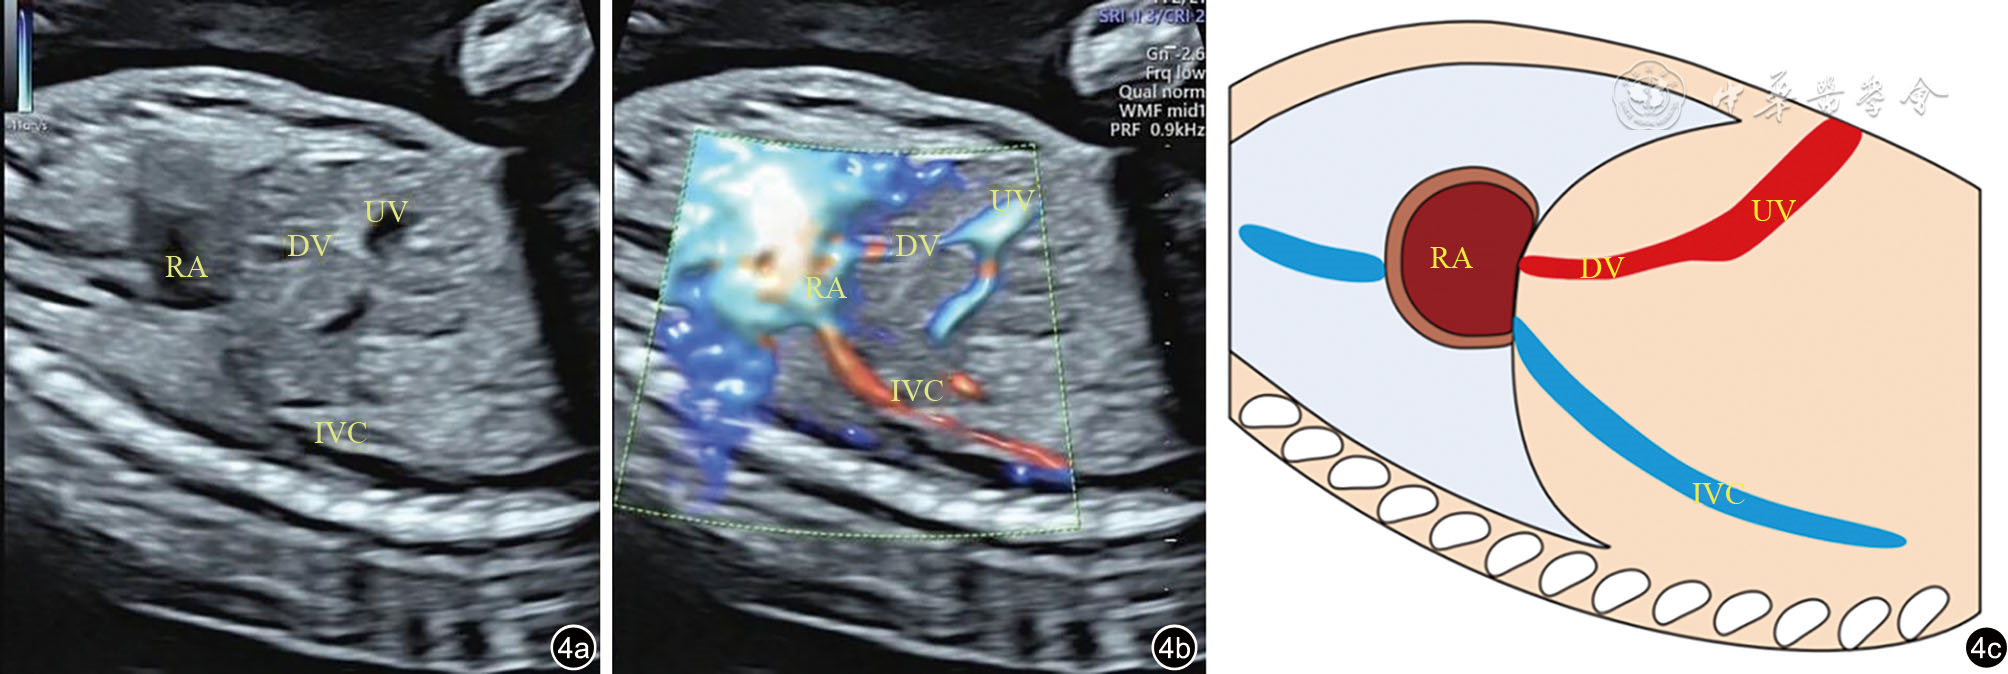

图4 静脉导管异常汇入右心房超声图像及示意图。图a、b为肋下视图显示静脉导管外观正常,静脉导管未经过下腔静脉直接汇入右心房;图c为静脉导管异常汇入右心房示意图 注:DV为静脉导管;IVC为下腔静脉;RA为右心房;UV为脐静脉